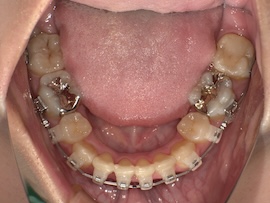

写真は撮っていないのでさらに1ヶ月後、

急に親知らずが出てきましたね。(笑)

無事に牽引ができたので、内側の装置も外れました。予定していたよりもかなり早く、牽引を始めてから約5ヶ月の時点です。